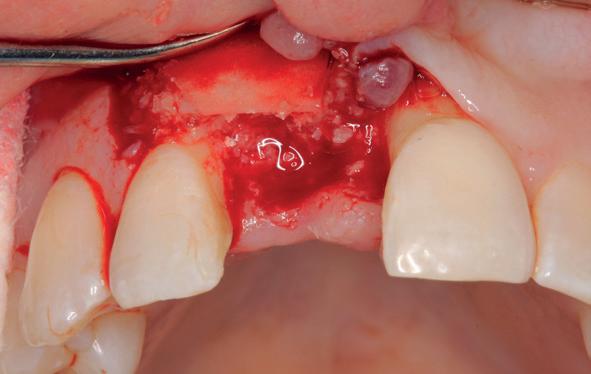

Implantologische behandelingen in het esthetische front vragen meer dan technische vaardigheid alleen. Ze vragen om overzicht, timing, vertrouwen en een team dat als vanzelf samenwerkt onder druk. Juist bij complexe casussen, waarin angst, infectie en hoge esthetische verwachtingen samenkomen, wordt zichtbaar hoe bepalend de rol van de tandartsassistent is.

Deze casus beschrijft een uitgebreide immediate implantaatbehandeling bij een patiënt die door meerdere collega’s werd geweigerd. Niet omdat de mogelijkheden ontbraken, maar omdat de complexiteit vroeg om een perfect afgestemde samenwerking. Het verhaal laat zien hoe de assistent in zo’n traject veel meer is dan een uitvoerende kracht of “mal”, maar een dynamische surgical guide die het proces mede stuurt, bewaakt en mogelijk maakt.De patiënt: wanneer alles samenkomt

Na het klinische onderzoek volgde het röntgenologisch traject. De CBCT liet precies zien wat we al vreesden: een front waarin het bot onregelmatig was, duidelijke radiolucenties rond de pijlers en een infectiegebied dat zich onder vrijwel de gehele brug had verspreid. Tegelijkertijd was er ook potentie. Net voldoende botstructuur om immediate implantaatplaatsing te overwegen, mits alles perfect gepland zou worden.